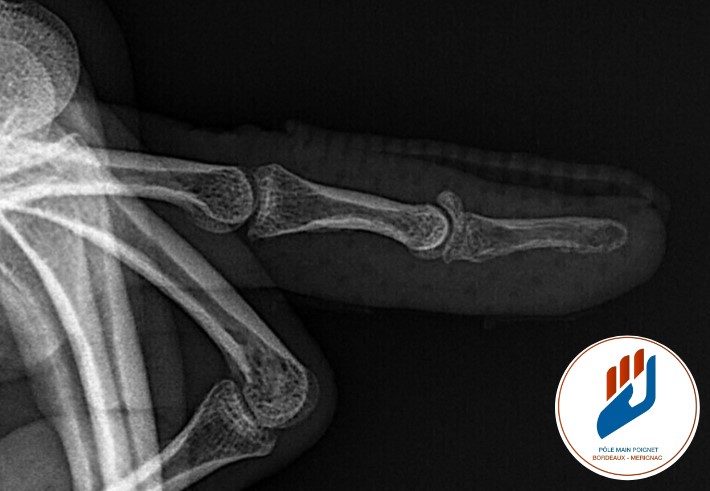

Établir le diagnostic

Le diagnostic est clinique : la dernière phalange du doigt fléchi, douloureux parfois et impossible à tendre activement.

Une radiographie complète l’évaluation pour vérifier qu’il n’existe ni subluxation, ni fragment osseux majeur.

Dans la plupart des cas, il n’y a pas besoin d’autres examens.